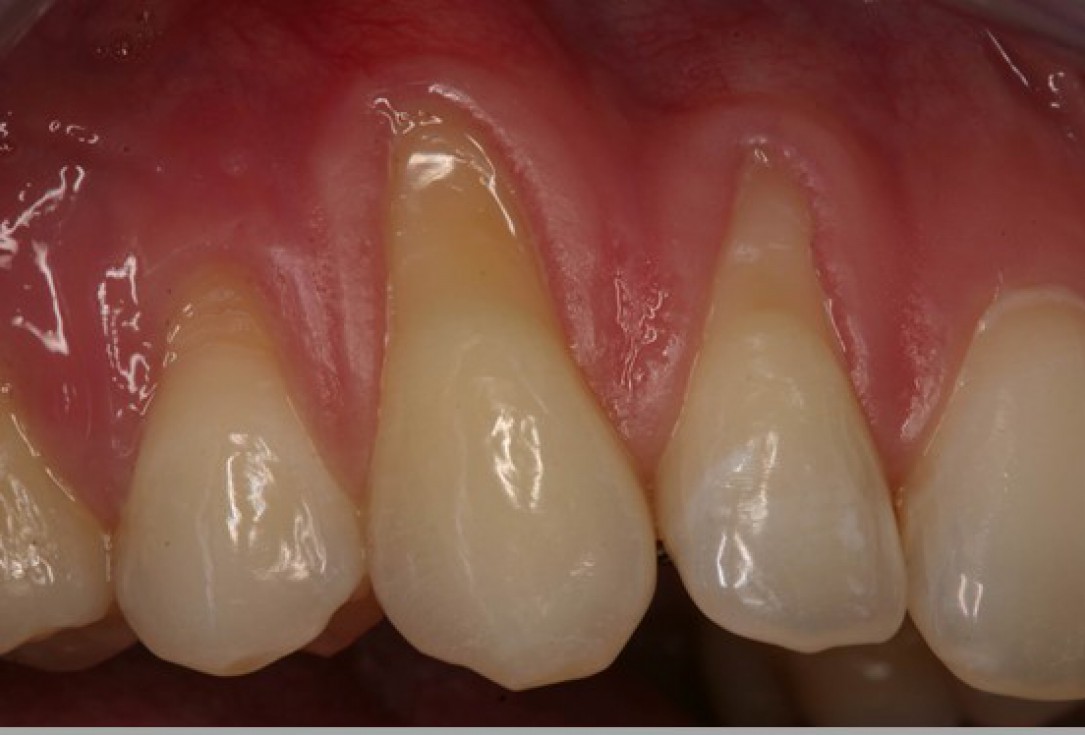

01/06 - Pre-surgical clinical situation. Multiple adjacent gingival recessions at teeth 12,13 and 14.Multiple gingival recessions treated with the modified coronally advanced flap in conjunction with mucoderm® - Prof. Dr. Dr. A. Kasaj

Pre-surgical clinical situation. Multiple adjacent gingival recessions at teeth 12,13 and 14.